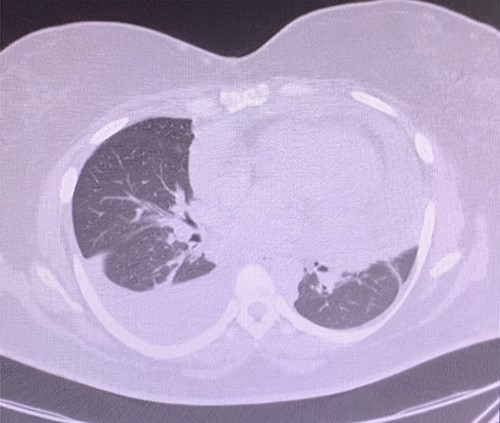

A 43-year-old woman with hypothyroidism and left lower extremity sarcoma that was treated with wide excision, and chemoradiotherapy treated with Doxorubicin, was performing routine screening with the oncologist which included a positron emission tomography/computed tomography (CT) scan, in which two small hypermetabolic nodules in the right upper lobe of the lung and a moderate to large pericardial effusion were found, effusion confirmed with an echocardiogram (Fig. 1). Upon findings, patient was sent to ER due to high suspicion of metastasis due to sarcoma history. She denied cough, shortness of breath, chest pain, palpitation, syncope or diaphoresis and related unintentional weight loss of 30 pounds in the last 3 months. Upon evaluation, patient was found with stable signs and there were no findings of pericardial tamponade. Chest CT scan was sent for further evaluation (Fig. 2).